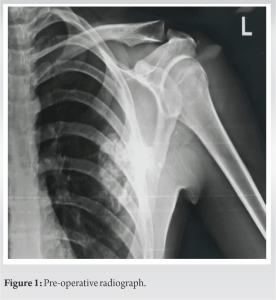

A 21-year-old man reported having a swelling over his left upper back region for the past 10 years, over which period it gradually increased in size. He had no other complaints. On examination, it was found that the overlying integument was normal, bony hard in consistency arising from the medial border of the scapula, non-tender, and approximately 7 × 7 cm in dimension. Moreover, winging of the scapula was observed, which was static as it did not increase with flexion of the arm against resistance. In addition, he had a complete range of motion without neurovascular compromise. Further assessments were conducted using roentgenography, computed tomography scan, and magnetic resonance imaging (Fig. 1, 2, 3, 4), through which two lesions were distinguished; a 70 × 55 mm exophytic tumor arising from the ventral wall of the body of the scapula directed posteromedially, scalloping the adjacent chest wall, and another similar lesion of 30 × 25 mm projecting laterally.